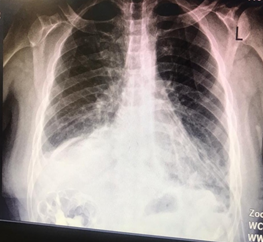

The patient has no history of major trauma or abdominal surgery, except for a history of trisomy 21 and left foot fracture, and is not taking any medication. At the emergency department, blood pressure was 125/75 mmHg, heart rate: 88 beats/min, O2 saturation: 92 %, respiratory rate: 18/min, and temperature: 37o C. The physical examination revealed abdominal tenderness in LUQ without rebound and guarding and reduced respiratory sound in the lower part of the left lung. The patient's ECG was normal. Abdominal and chest x-rays showed that the loops of the colon were located in the left hemithorax (Figure 1). In further examination, a computed tomography scan of the thorax and abdomen with oral and intravenous contrast revealed a large diaphragmatic hernia with a displacement of the left kidney, spleen, and parts of the small intestine and colon into the thoracic cavity (Figure 2). The patient had normal lab tests except WBC 10500 with PMN 85%. In echocardiography, LVEF was reported 45%, without ASD and VSD with moderate MR.

Figure 1 Loops of colon were located in the left hemithorax.